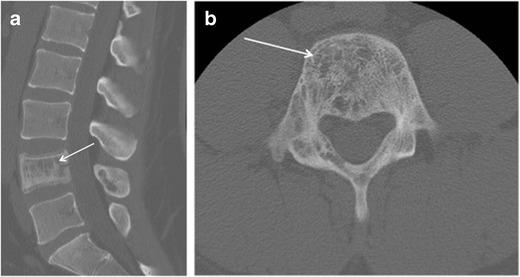

Haemangiomas of the vertebrae, usually regarded as having little or no consequence, may display aggressive features, including extension into the extradural space, and cause significant neurological symptoms and signs necessitating treatment. Extraosseous haemangiomas in an extradural or intradural extramedullary location are a rare entity. Here we review our radiologic and pathologic experience of osseous haemangiomas with extradural extension and primary extradural and intradural extramedullary haemangiomas. Magnetic resonance imaging plays a pivotal role in the characterisation of spinal haemangiomas, with typical imaging features including T1 and T2 signal hyperintensity. Atypical and aggressive imaging features are also described. Spinal angiography may be required to differentiate haemangiomas from non-vascular lesions. This is a rare and unusual entity, and should be considered as a differential diagnosis for some extramedullary masses.

椎骨血管瘤通常被认为影响不大或无影响,但可能呈现侵袭性特征,包括延伸至硬膜外间隙,并导致严重的神经症状和体征,需要进行治疗。硬膜外或硬膜内髓外位置的骨外血管瘤是一种罕见的实体。在此,我们回顾了骨血管瘤伴硬膜外延伸以及原发性硬膜外和硬膜内髓外血管瘤的放射学和病理学经验。磁共振成像在脊柱血管瘤的特征性诊断中起关键作用,典型的成像特征包括T1和T2信号高增强。还描述了非典型和侵袭性成像特征。可能需要进行脊髓血管造影以区分血管瘤与非血管性病变。这是一种罕见且不寻常的实体,应被视为某些髓外肿块的鉴别诊断。